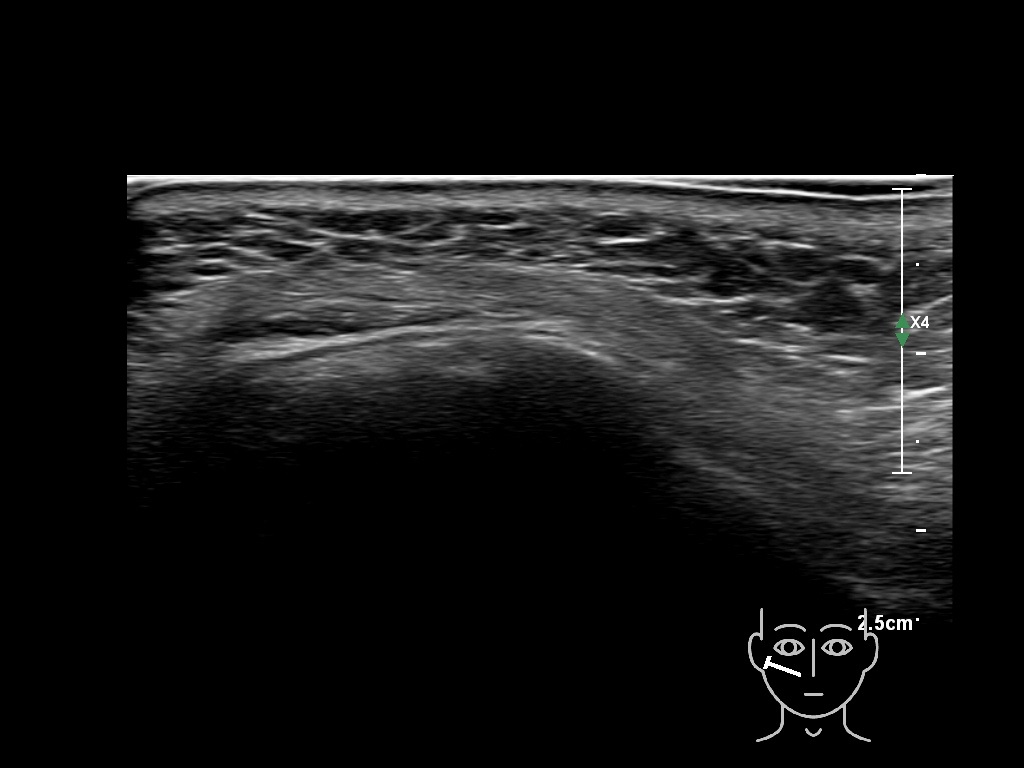

Draw in the image on the right where the fillers are located. To check if your answer is correct, please click on the secondary image.

Draw in the second image below where the fillers are located. To check if your answer is correct, swipe the first image to the right.